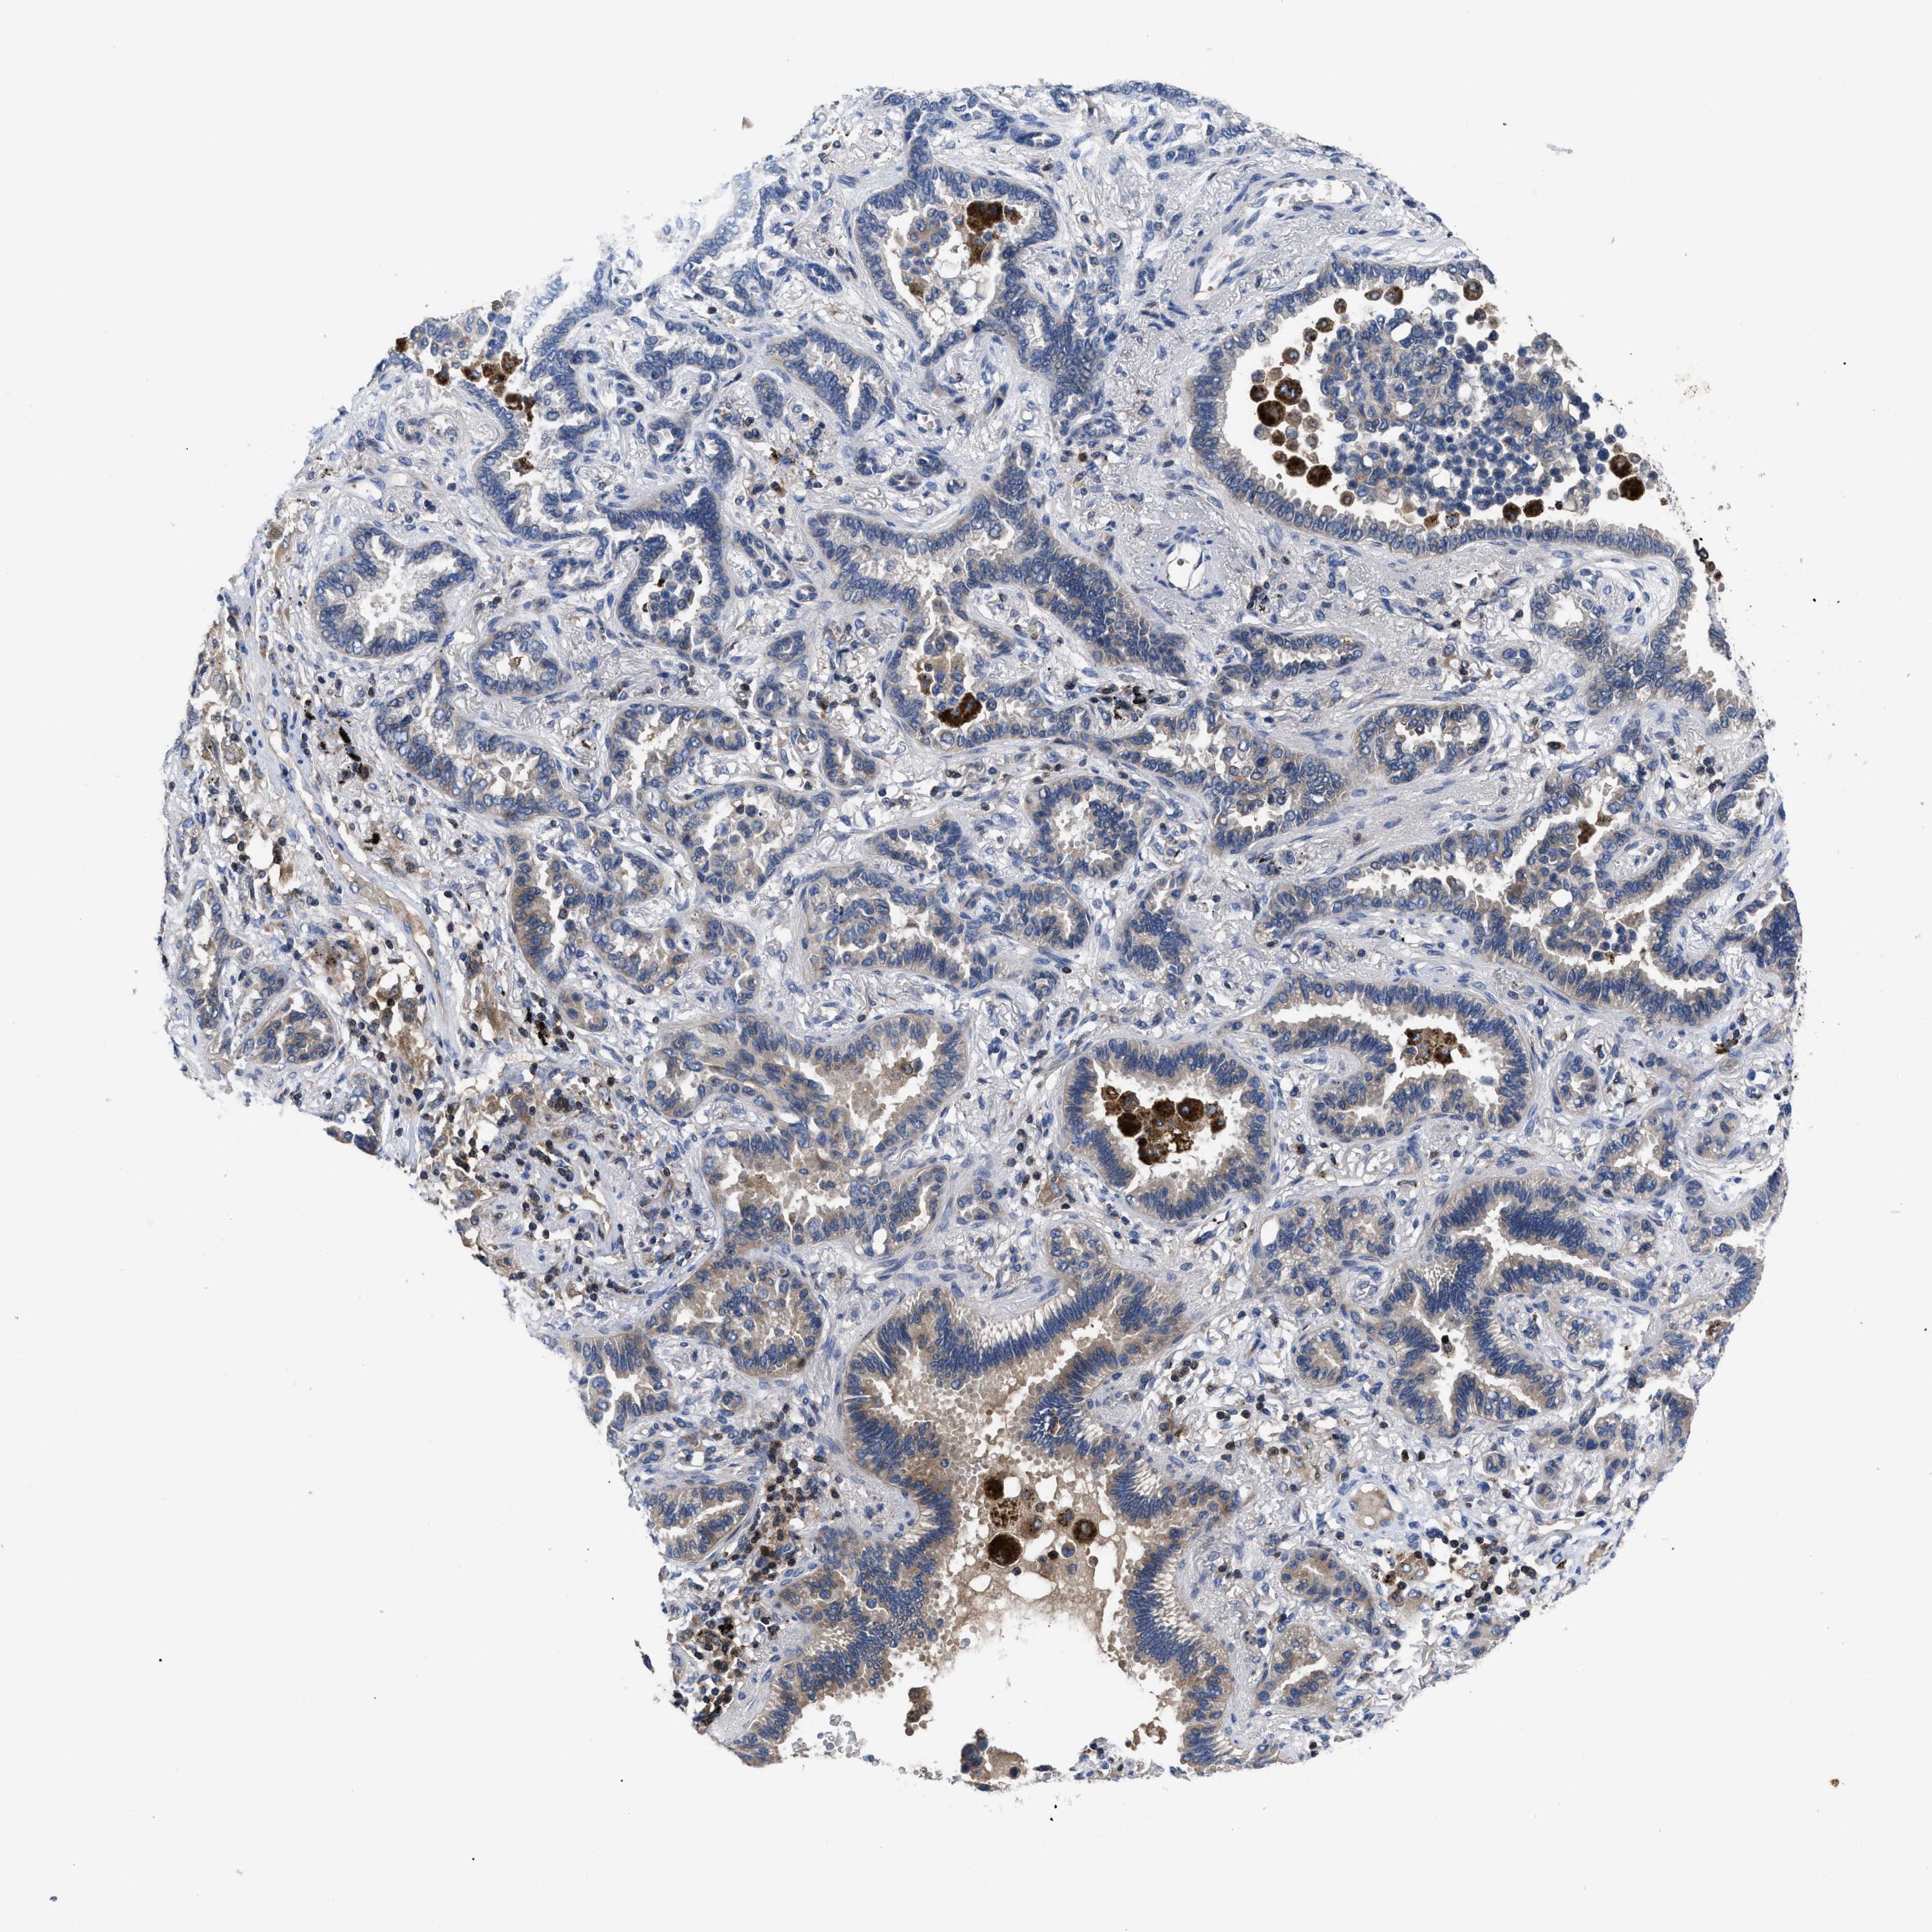

LUNG ADENOCARCINOMA (VALIDATION) - Interactive survival scatter ploti

The Survival Scatter plot shows the clinical status (i.e. dead or alive) for all individuals in the patient cohort, based on the same data that underlies the corresponding Kaplan-Meier plots. Patients that are alive at last time for follow-up are shown in blue and patients who have died during the study are shown in red.

The x-axis shows the expression levels (FPKM) of the investigated gene in the tumor tissue at the time of diagnosis. The y-axis shows the follow-up time after diagnosis (years). Both axes are complimented with kernel density curves demonstrating the data density over the axes. The top density plot shows the expression levels (FPKM) distribution among dead (red) and alive patients (blue). The right density plot shows the data density of the survived years of dead patients with high and low expression levels respectively, stratified using the cutoff indicated by the vertical dashed line through the Survival Scatter plot. This cutoff is automatically defined based on the FPKM cutoff that minimizes the p-score. The cutoff can be changed by dragging the vertical line or by entering a cutoff value in the square labeled "Current cut-off".

Under the Survival Scatter plot the p-score landscape (black curve; left axis) is shown together with dead median separation (red curve; right axis). Dead median separation is the difference in median mRNA expression between patients who have died with high and low expression, respectively. It is calculated as follows: median FPKM expression of dead patients with high expression - median FPKM expression of dead patients with low expression. This is intended to aid the user in visually exploring custom cutoffs and the associated p-scores and dead median separation.

Individual patient data is displayed and can be filtered by clicking on one or more of the category buttons on the top of the page. Categories describing expression level and patient information include: high, low, alive, dead, female, male and tumor stages. The scale of the x-axis can be toggled between linear and log-scale by clicking on the "x log" button. Mouse-over function shows TCGA ID, patient information and mRNA expression (FPKM) for each patient.

& Survival analysisi

Kaplan-Meier plots summarize results from analysis of correlation between mRNA expression level and patient survival. Patients were divided based on level of expression into one of the two groups "low" (under cut off) or "high" (over cut off). X-axis shows time for survival (years) and y-axis shows the probability of survival, where 1.0 corresponds to 100 percent.

YBEY is not prognostic in Lung Adenocarcinoma (validation)

: 18

Average pTPM 14.8

Number of samples 105